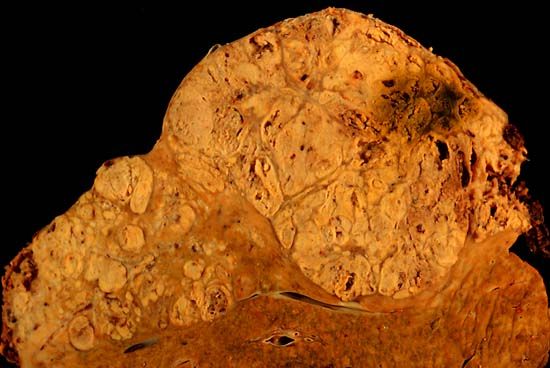

Photo caption: A section from a formalin-fixed specimen taken from an individual who died shows hepatocellular carcinoma occupying much of the volume of a cirrhotic liver. (Public domain image)

Hepatocellular carcinoma (HCC), a form of liver cancer that is the third leading cause of cancer deaths worldwide, is surging in the United States. Cases have tripled in the last two decades, occurring primarily among people age 50. The spike is largely due to hepatitis C viral infections acquired decades prior.